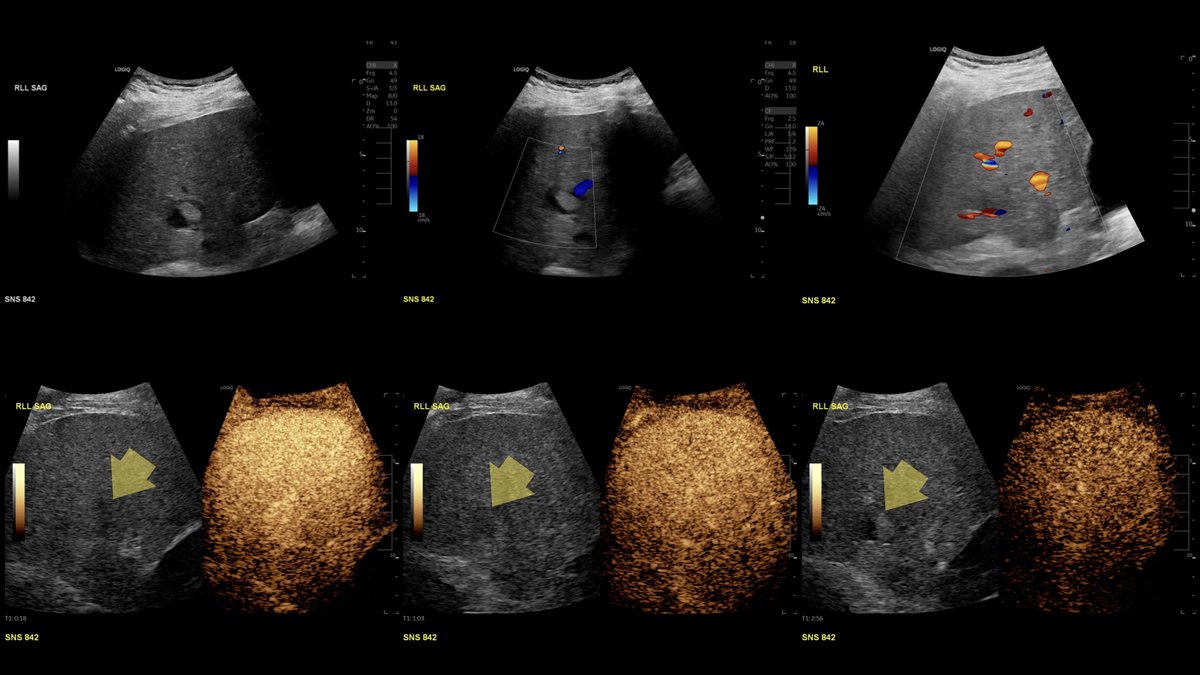

Great job! Contrast-enhanced US performed to assess for intralesional arterial phase hyperenhancement and washout... diagnosis?

All right, all right... Where is the spleen? This patient is status post splenectomy for trauma. MRI performed 5 years later confirming benign vs indolent etiology... this is... Mesenteric SPLENOSIS! @BrighamRad @FOAMrad @SAR_RFS @futureradres @ARRS_Radiology @Abdominal_Rad